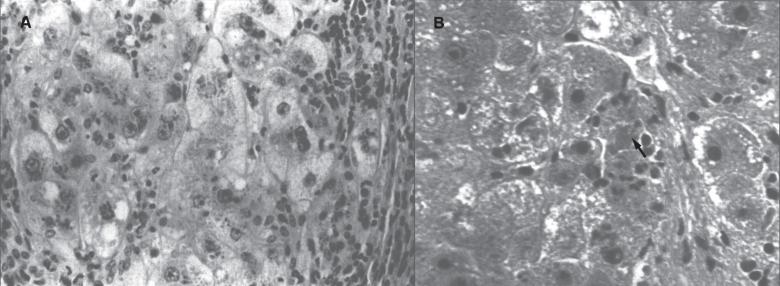

Trace elements are chemical elements needed in minute amounts for normal physiology. Some of the physiologically relevant trace elements include iodine, copper, iron, manganese, zinc, selenium, cobalt and molybdenum. Of these, some are metals, and in particular, transition metals. The different electron shells of an atom carry different energy levels, with those closest to the nucleus being lowest in energy. The number of electrons in the outermost shell determines the reactivity of such an atom. The electron shells are divided in sub-shells, and in particular the third shell has s, p and d sub-shells. Transition metals are strictly defined as elements whose atom has an incomplete d sub-shell. This incomplete d sub-shell makes them prone to chemical reactions, particularly redox reactions. Transition metals of biologic importance include copper, iron, manganese, cobalt and molybdenum. Zinc is not a transition metal, since it has a complete d sub-shell. Selenium, on the other hand, is strictly speaking a nonmetal, although given its chemical properties between those of metals and nonmetals, it is sometimes considered a metalloid. In this review, we summarize the current knowledge on the inborn errors of metal and metalloid metabolism.

微量元素是正常生理功能所需的微量化学元素。一些与生理相关的微量元素包括碘、铜、铁、锰、锌、硒、钴和钼。其中,有些是金属,特别是过渡金属。原子的不同电子壳层具有不同的能级,最靠近原子核的电子壳层能量最低。最外层电子的数量决定了该原子的反应活性。电子壳层又分为子壳层,特别是第三壳层有s、p和d子壳层。过渡金属被严格定义为原子具有不完全d子壳层的元素。这种不完全的d子壳层使它们易于发生化学反应,特别是氧化还原反应。具有生物学重要性的过渡金属包括铜、铁、锰、钴和钼。锌不是过渡金属,因为它有一个完整的d子壳层。另一方面,严格来说硒是一种非金属,尽管鉴于其化学性质介于金属和非金属之间,它有时被视为类金属。在本综述中,我们总结了目前关于金属和类金属代谢先天性缺陷的知识。